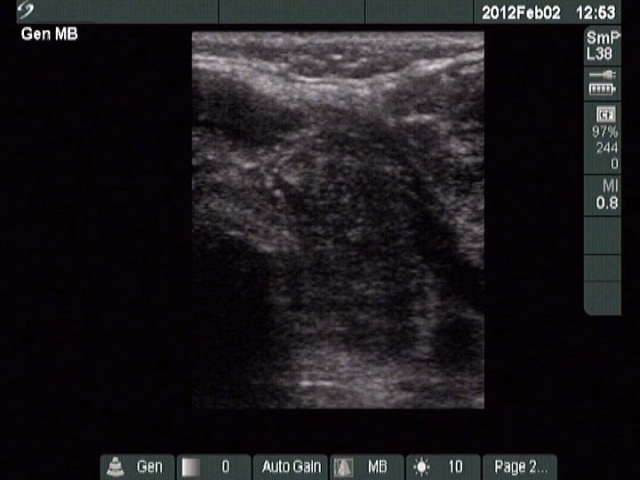

Ultrasonography: Both lobes were deeply hypoechoic. There was a large lymph node just lateral to the left thyroid lobe. The node had a central scar and presented echonormal discrete fields as well. It is worth noting that the left thyroid lobe was more inhomogeneous compared to the other thyroid lobe. This inhomogeneity made the appearance of the left lobe close to the tumorous lymph node.

On the ultrasound presentation, it was not evident that the thyroid also has malignant lesion, but the histopathology disclosed that the lymphoma was present even within the thyroid.